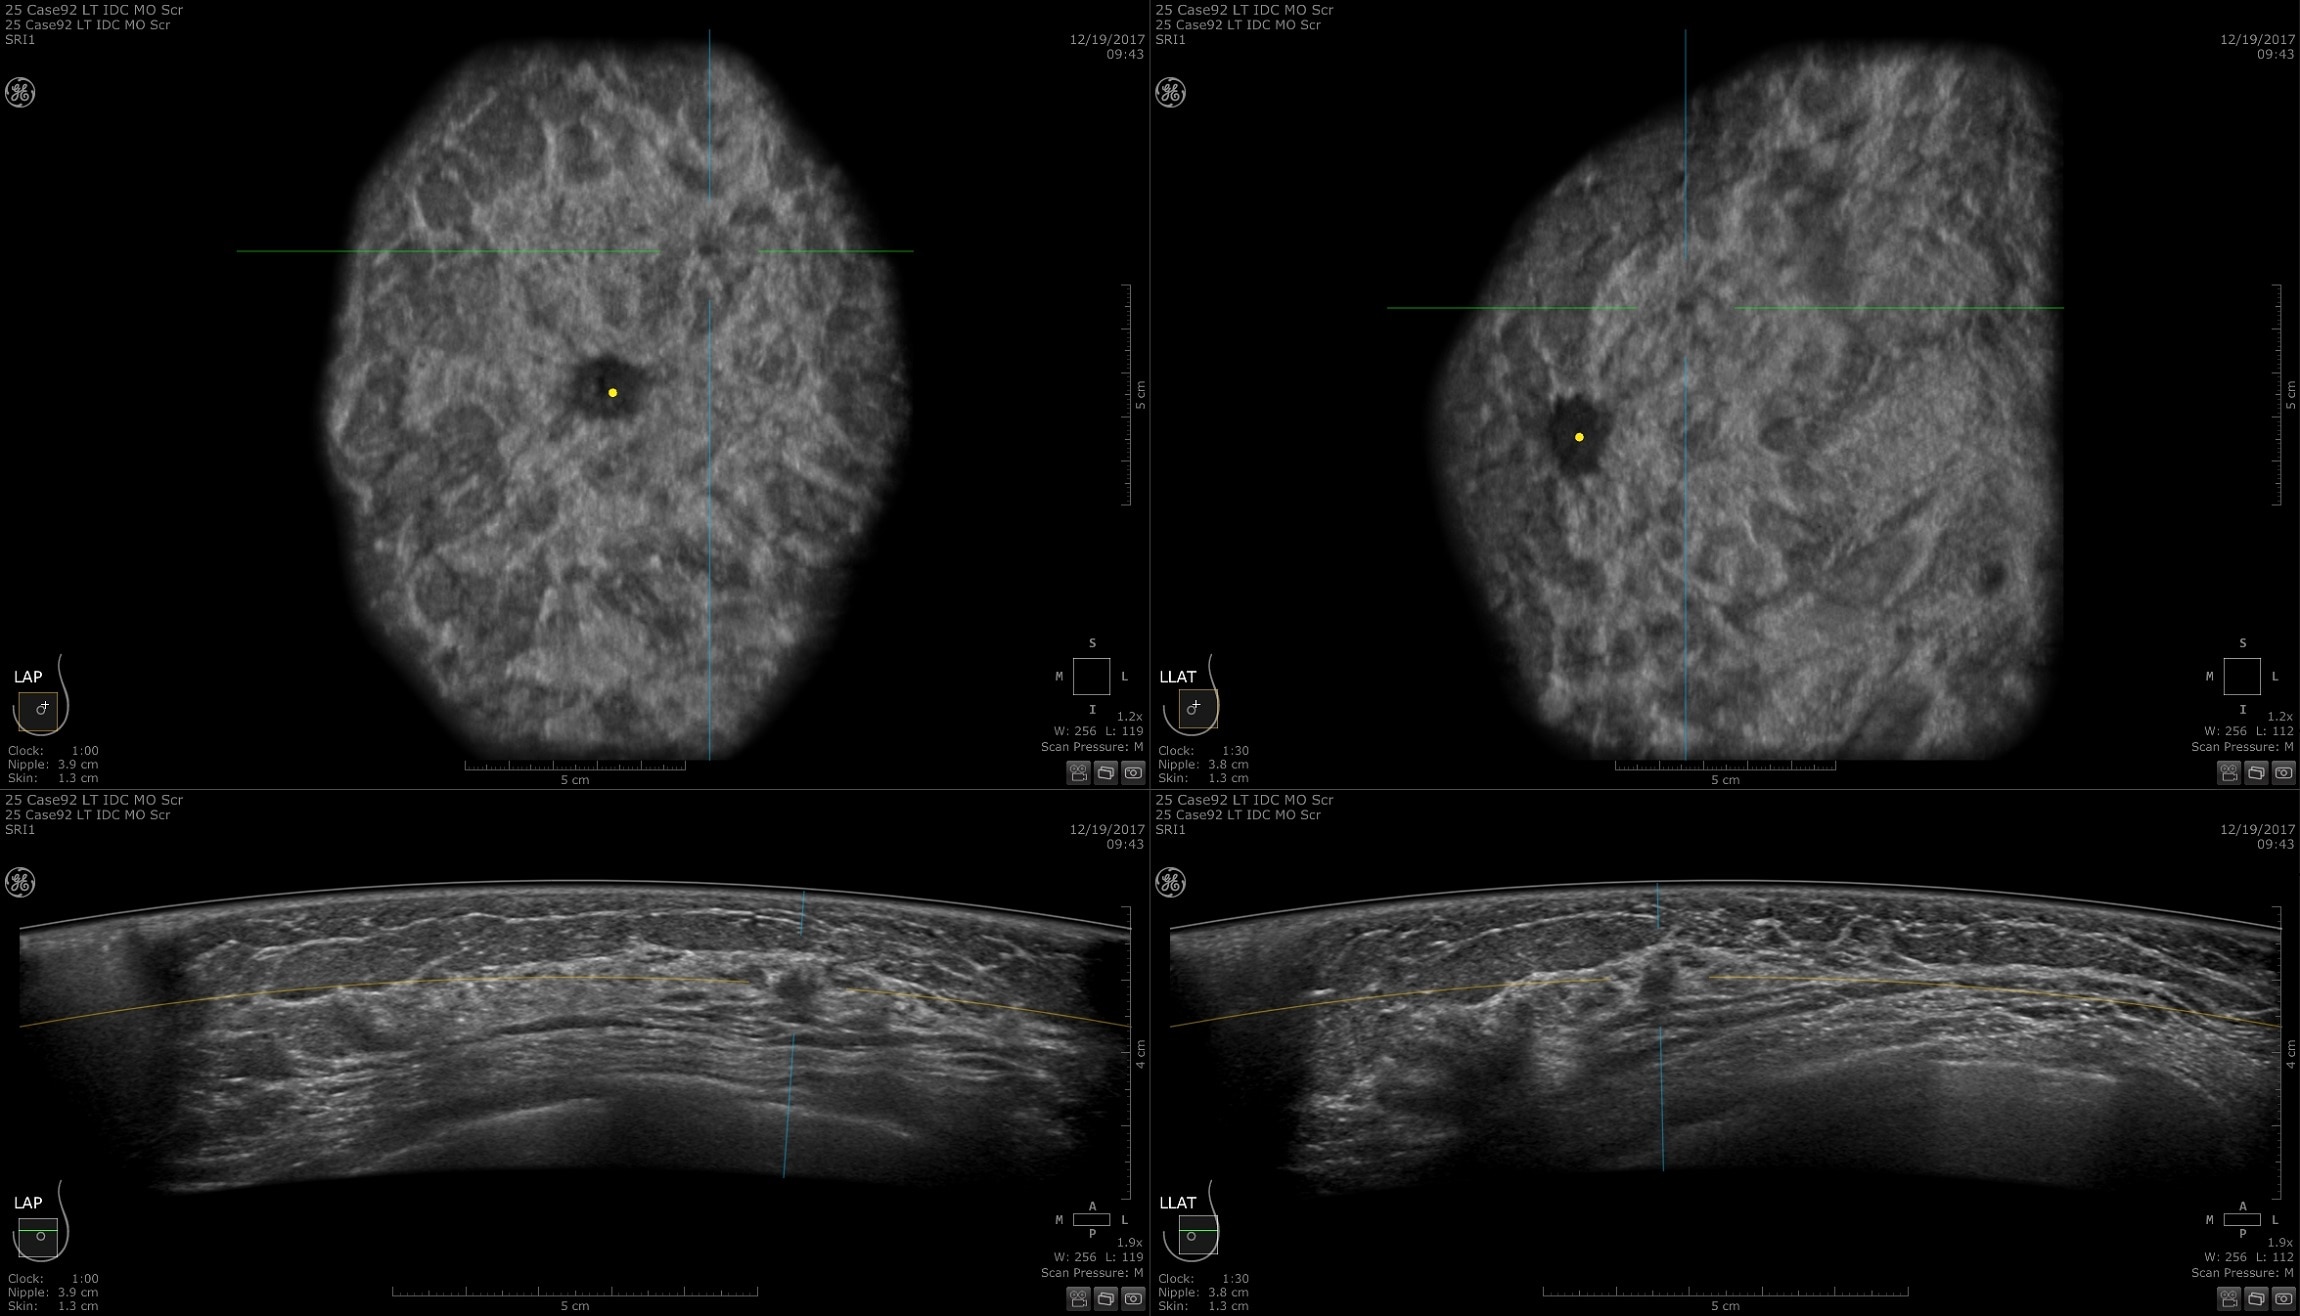

DIAGNOSIS & STAGING

Lesion characterization for confident staging in dense breasts

Invenia ABUS 2.0 uses the latest ultrasound innovations and AI based solutions to help improve precise diagnosis and elevate clinical confidence.